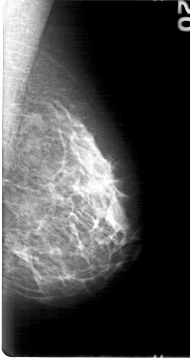

D_4030_1.LEFT_MLO

LEFT_MLO LINES 5386 PIXELS_PER_LINE 2836 BITS_PER_PIXEL 12 RESOLUTION 43.5 NON_OVERLAY